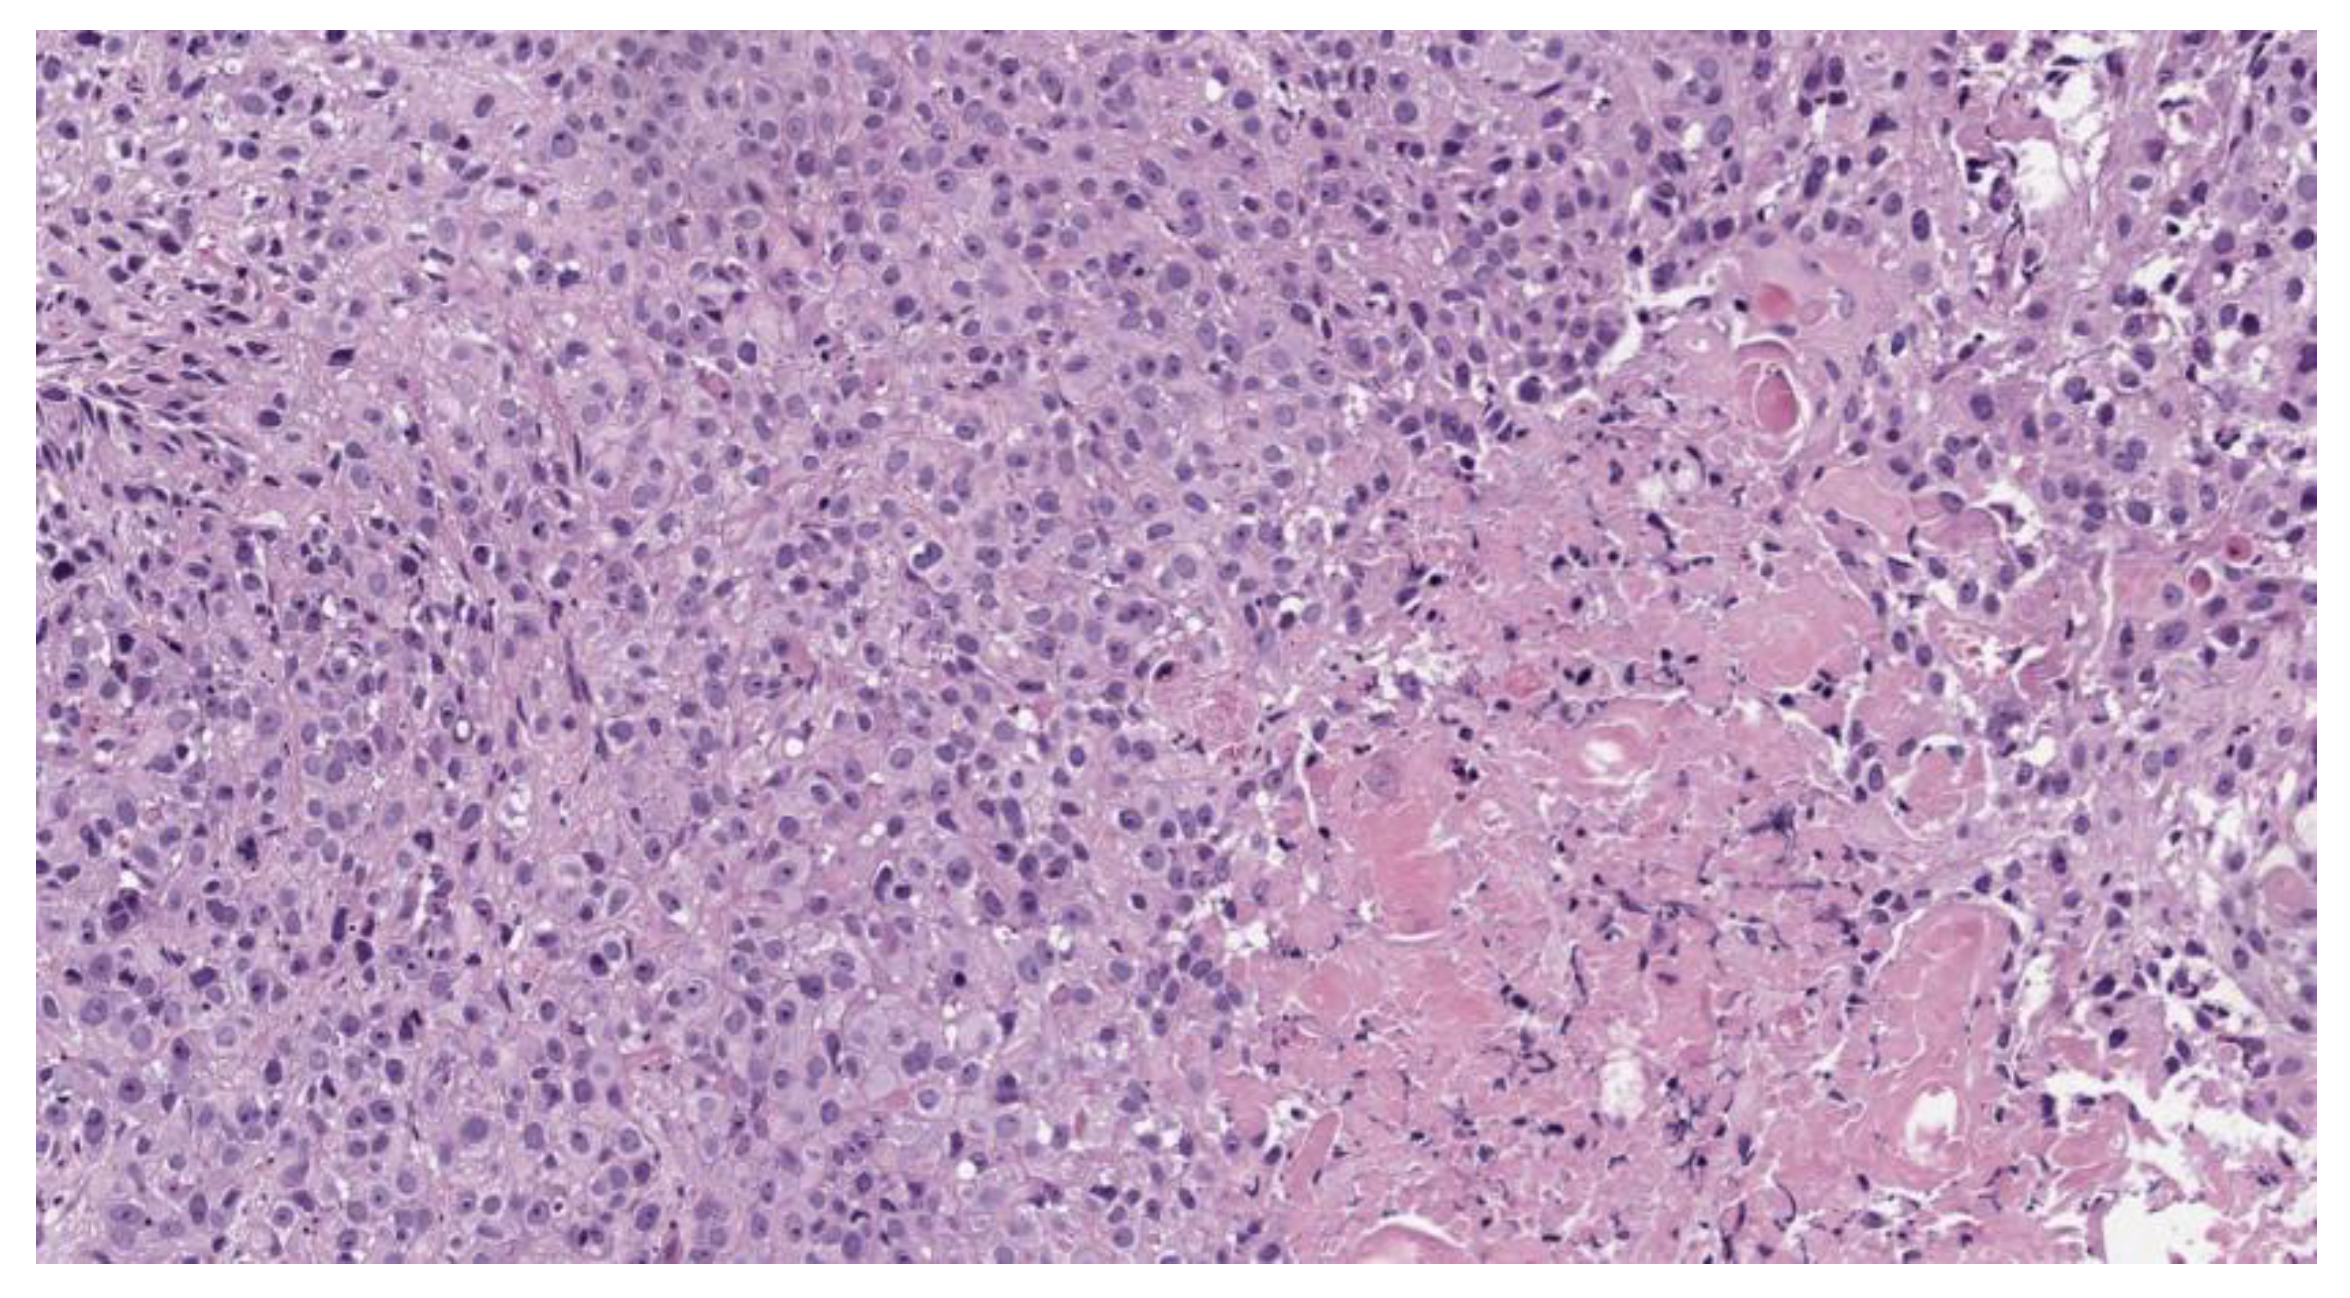

A pathohistological analysis of the biological tissue taken from the tumor site of the right vocal cord is displayed on the Figure 6 and Figure 7.

A histological analysis showed squamous cell carcinoma, G2, before PDT (Figure 6). The microscopic analysis of biopsy sample demonstrated changes in the tumor cells with paretic plethora of the blood vessels of the microvasculature with the formation of blood clots after PDT (Figure 7a,b). There is a positive dynamic observation in the form of complete regression of the tumor.

Figure 6. Moderately differentiated squamous cell carcinoma, G2; staining with hematoxylin-eosin, *100 magnification.

Figure 7. Moderately differentiated squamous cell carcinoma, G2, after PDT; staining with hematoxylin-eosin: (a) *400 magnification; (b) *100 magnification.